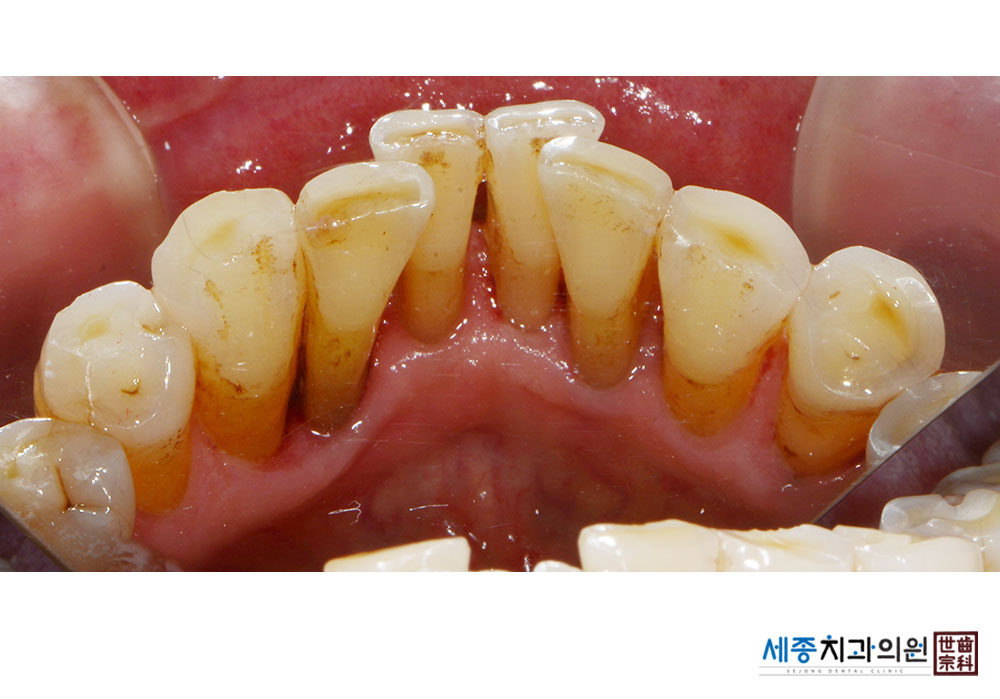

[스케일링] 치주질환 예방 스케일링

치료전 : 2021-01-13

치료후 : 2021-01-13

가글마취&저주파 스켈러를 사용한 스케일링